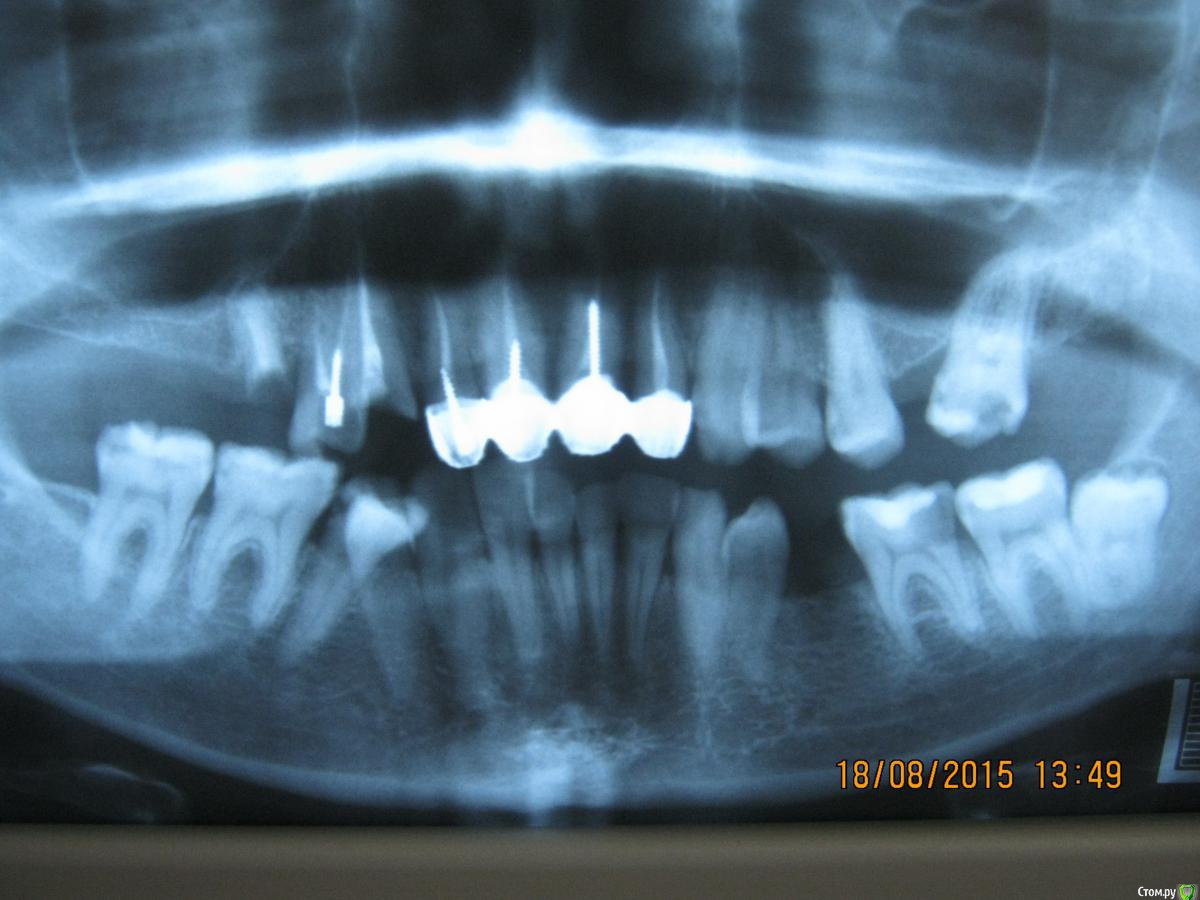

SeregaStomatolog Опубликовано 18 августа, 2015 Поделиться Опубликовано 18 августа, 2015 Добрый вечер уважаемые коллеги!В клинику обратилась пациентка с такой ситуацией во рту.Подскажите пожалуйста что можно сделать и с чего начать. Ссылка на комментарий

SeregaStomatolog Опубликовано 18 августа, 2015 Автор Поделиться Опубликовано 18 августа, 2015 Во-первых она хочет нормально улыбаться,не стесняясь отсутствующего клыка.Во-вторых она хочет нормально жевать,т.к. отсутствие 1.7,1.6 не позволяет это делать.Я сразу сказал пациентке что вариантов без ортодонтии мало (если они вообще есть) и обещать ничего не стал.Случай сложный,поэтому хочется узнать в принципе,на будущее,какие варианты лечения возможны (если можно по подробнее).Пока что я снял слепки,отлил модели-пошел за советом к коллегам в другую клинику-все настаивают на ортодонтии.Теперь вся надежда на Вас коллеги,подскажите что можно придумать более менее приемлемое без ортодонтии. Ссылка на комментарий

SeregaStomatolog Опубликовано 18 августа, 2015 Автор Поделиться Опубликовано 18 августа, 2015 Сделав как хочет пациентка вы не получите красивый результат, которого она ждет! и получится что вы не смогли реализовать ее мечты , а значит доктор неахти)) да и вы не особо результатом будете довольны, вам это надо? Если в эстетике проблем нет, восстановите функцию. Ненужное удалить, длинные зубы дэпульпировать, укоротить ну и коронуйте))Мне кажется если я возьмусь,то все равно не буду результатом доволен,т.к. все реализовать не получится.Самая большая проблема в области отсутствующих 1.6,1.7-зубо-альвеолярное удлинение 4.6,4.7 настолько велико,что они практически касаются слизистой в области 1.6,1.7. Ссылка на комментарий